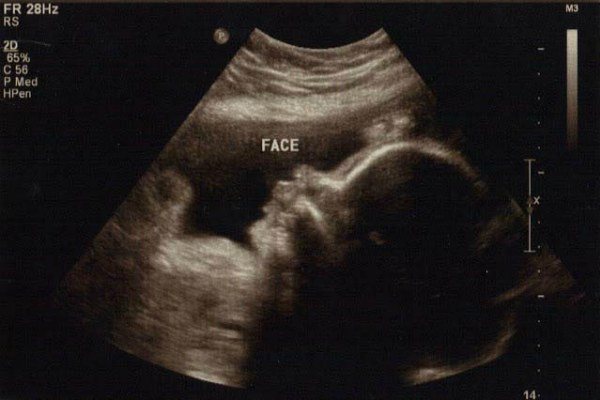

На 30-й неделе беременности врачи отмечают, что рост и вес ребенка становятся важными показателями его развития. В среднем, на этом этапе плод достигает длины около 39 см и веса около 1,3 кг. Специалисты подчеркивают, что эти параметры могут варьироваться в зависимости от индивидуальных особенностей матери и плода. Важно, чтобы будущая мама следила за своим питанием и уровнем физической активности, так как это напрямую влияет на здоровье ребенка. Врачи рекомендуют регулярно проходить УЗИ и контролировать динамику роста плода. На этом сроке также активно формируются жизненно важные органы, и любые отклонения могут потребовать дополнительного внимания. Поддержка со стороны медицинских специалистов и соблюдение рекомендаций помогут обеспечить нормальное развитие малыша.

Живот на 30-й неделе беременности фото: